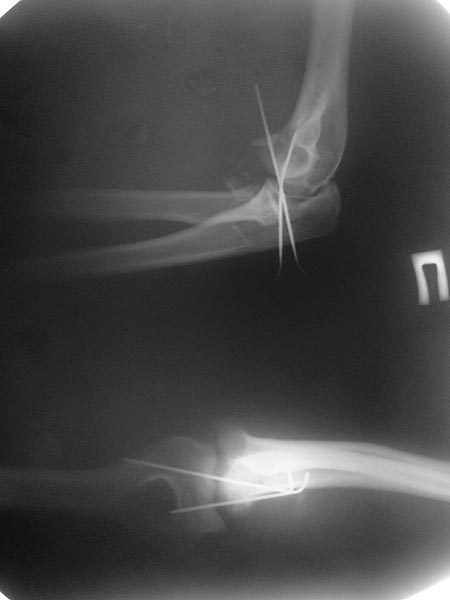

Перевели пациентку (работающая женщина 51 г.) из другого района, где ей

10 дней назад вправили вывих предплечья. На данный момент имеется вот

такая картина. Что делать с головкой лучевой кости? Опыт лечения таких

повреждений мал, поэтому просим помощи. КТ выполнить не можем ввиду

неисправности последнего. Спасибо!